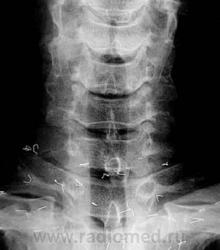

Передний снимок шейного отдела позвоночника. Множественные фрагменты акупунктурных игл в подкожной клетчатке верхней грудной области.

Нижнегрудной отдел позвоночника. Бесчисленные фрагменты акупунктурных игл в подкожной клетчатке спины.